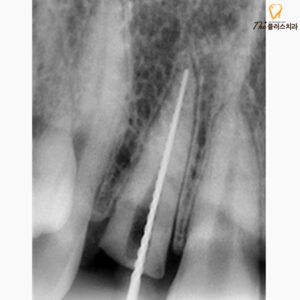

환자분께서는 사고로 인해 외상을 입으셨고,

오른쪽 두 번째 앞니 부분이

치아머리가 부러진 상태로 오셨습니다.

치아재식술은 문제가 있는 치아를

먼저 발치하게 됩니다.

이때 최대한 치아의 손상이 없어야 하고,

뿌리가 부러지지 않아야 성공률이 높습니다.

치아를 조심스럽게 발치한 후에는

치아 재식술을 통해

치아 뿌리 끝을 잘라내고

거꾸로 신경관을 치료하고,

특수한 치과 재료를 채우게 됩니다.